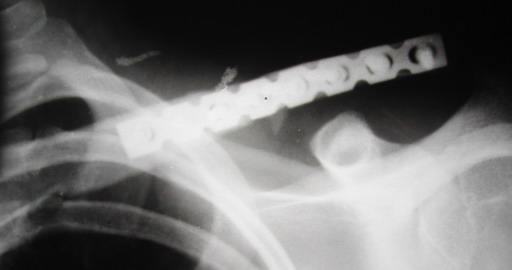

В приложении проект наших тезисов на съезд и клинический пример: Пациентка 23 лет поле неэффективного оперативного лечения (4 нед.) перелома ключицы спицей (была оперирована в С-Петербурге)(снимок после удаления спицы) и результат закрытого БИОС..

Один из вариантов, что удалось быстро найти, позже еще найду, но схема примерно такая (первое

вложение).

Мужик кочегар, срок нетрудоспособности 7 недель. Наружную конструкцию сняли через 3 недели. Далее без иммобилизации. Погруженную спицу можно убрать и через несколько месяцев, если жить не мешает.